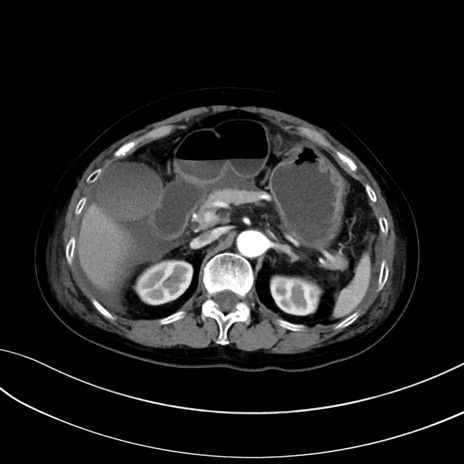

(冠状断像)1日半後